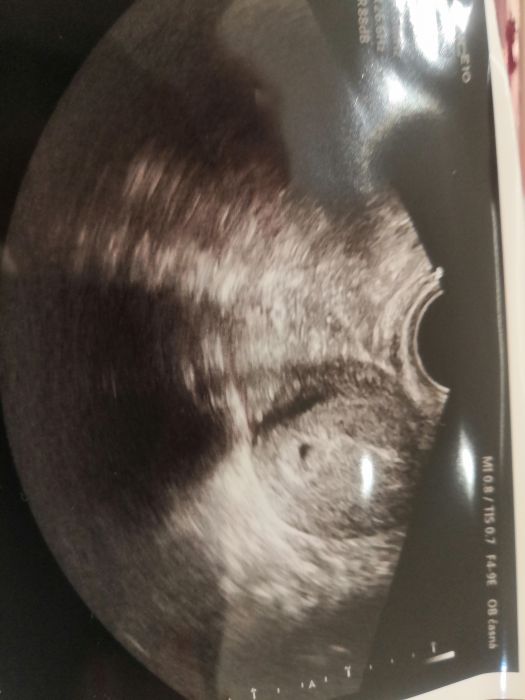

Tak prý je podle ultrazvuku menší.. Takže mám jen černou tečku.. Chtěl mě vidět za týden, ale to jsou vánoce.. Další kontrolu mám 2.1. Ale jsem ofiko těhule.. Jupiii..